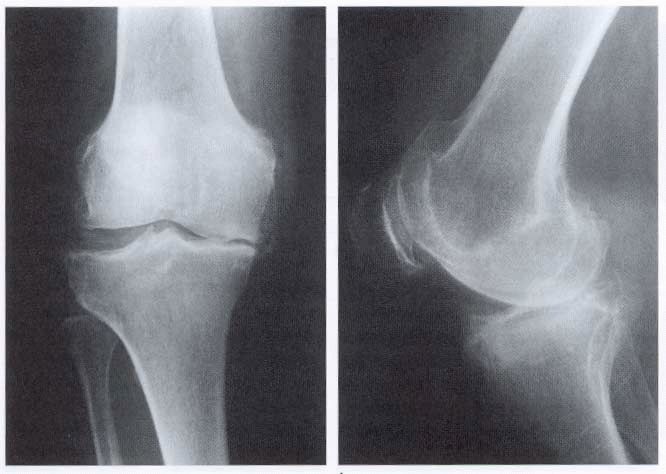

Диагностические мероприятия

Для создания эффективного терапевтического плана необходимо провести всестороннюю диагностику. Это поможет установить стадию заболевания и степень поражения коленного сустава. Процесс начинается с осмотра у врача, анализа клинической картины, выслушивания жалоб пациента и изучения анамнеза.

Во время осмотра врач измеряет длину ног и оценивает состояние мышечной ткани. Для этого пациента просят выполнить несколько простых физических упражнений. В зависимости от ситуации могут быть рекомендованы следующие виды диагностических исследований:

Существует три основные стадии остеоартроза коленного сустава: первая стадия характеризуется легкими болями и незначительными изменениями на рентгенограммах; во второй стадии боли становятся более выраженными, появляются ограничения в движении и изменения в суставном хряще; третья стадия сопровождается сильной болью, значительным ограничением подвижности и выраженными изменениями на рентгене, включая остеофиты и сужение суставной щели.